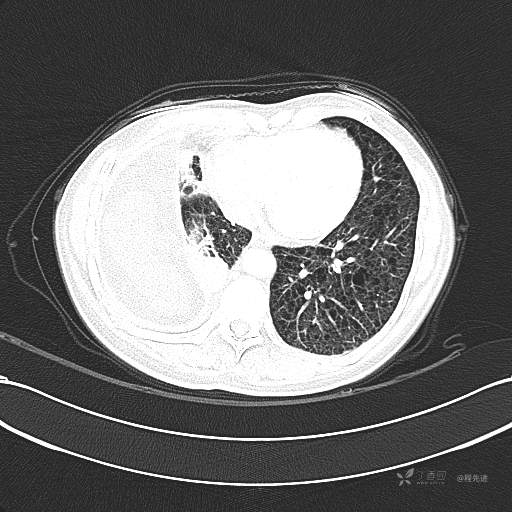

患者性别:女

患者年龄:51岁

简要病史:胸闷半年

肺淋巴管肌瘤病 (7)

乳糜胸 (8)